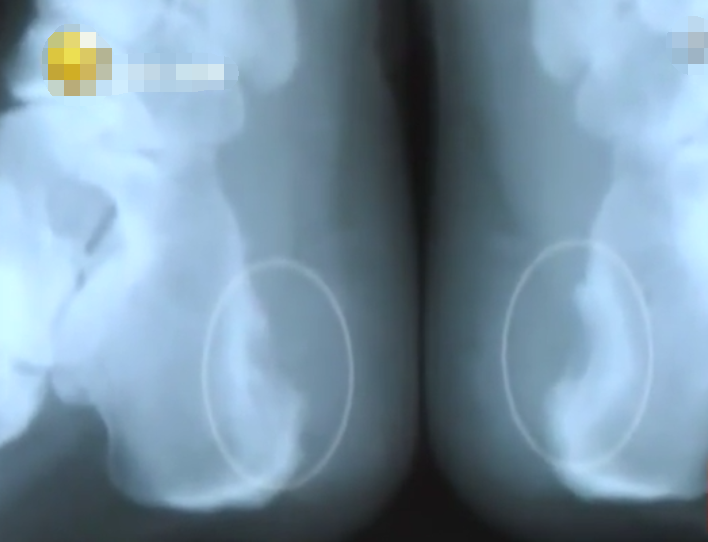

夏主任拿著小紅足部透視的片子仔細(xì)端詳。

發(fā)現(xiàn)她足底腳后跟的骨頭,全都變得像小石子一樣細(xì)碎。

除此之外,一大截骨小梁也全部被磨損掉了。

后跟的骨頭不再是凸出的一條流暢弧線,而是凹進(jìn)去一塊。

醫(yī)生介紹說,足跟底部的這塊骨頭,是承受自身身體重量大的一塊骨頭。

在這里墊一塊東西,破壞了正常的組織機(jī)構(gòu)。

對足底乃至整個身體的穩(wěn)定性和承受力影響都大。

久而久之,身體在吸收和同化這塊異物的同時,也把周圍的組織包括骨頭破壞了。